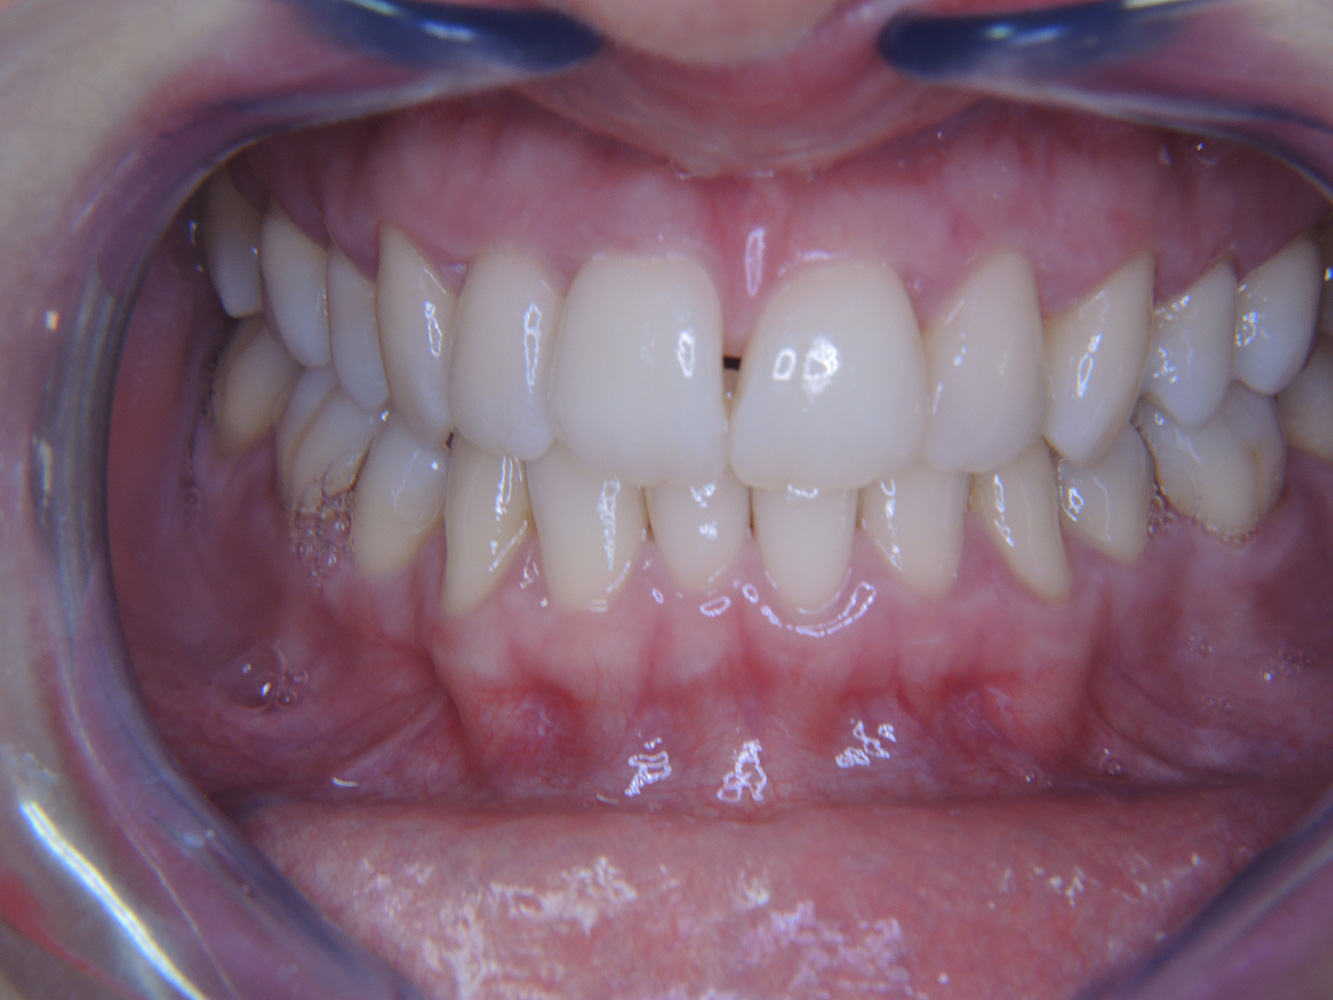

In the medical history, the 55-year-old patient states that he has no systemic disease and is not taking any medication. The patient’s lifestyle is similarly unremarkable. The patient has a few tooth restorations and two implants (2nd and 4th quadrants). On the basis of current findings, gingivitis is identified in an otherwise stable periodontal condition on the reduced periodontium (stage III, grade A). more

The healthy patient with pre-existing periodontal disease & peri-implantitis

A 52-year-old patient presents at a preventive care session. The patient has no systemic disease and is not taking any medication. He has had various dental treatments and also has two active carious lesions. In addition, the patient has four implants (2nd, 3rd and 4th quadrants). He is revealed to have early periodontal disease (stage IV, grade B). His periodontal condition is stable; a probing depth of Probing depths (ST) of 5 mm is only evident at the implant in region 36. Gingivitis is also identified. more

The healthy patient with early periodontal disease